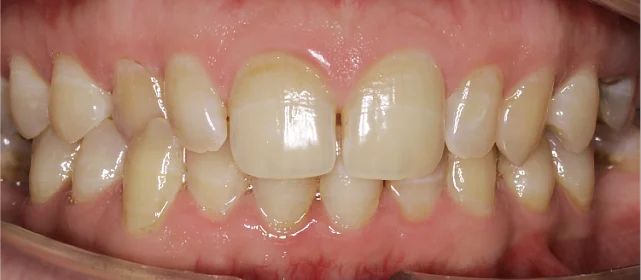

Проблема: Пациентка обратилась с жалобами на неровные зубы и неправильный прикус. Челюсти смыкались некорректно, зубы стояли со смещением. Часть зубов нуждалась в восстановлении коронками, но ставить их на кривой ряд с неправильным прикусом значит заведомо сократить им срок службы. Нагрузка будет распределяться неравномерно, и конструкции быстро выйдут из строя. Поэтому первый этап — ортодонтия, второй — протезирование.

Мне было важно понимать план целиком, что да как, прежде, чем стартовать лечение. Мария Сергеевна на первой же консультации объяснила: сначала выравниваем, потом коронки и почему именно в таком порядке. 28 месяцев в брекетах — не скажу, что это было легко, особенно первые пару недель. Но потом привыкаешь и перестаёшь обращать внимание. Сейчас зубы ровные, далее будем ставить коронки!

Двухэтапный случай: сначала ортодонтия, потом протезирование. Ставить коронки при неправильном прикусе нельзя — нагрузка ляжет неравномерно, конструкции не прослужат долго. Брекеты H4 отработали за 28 месяцев, ряд подготовлен. Ретенционные капы сознательно делаем после коронок — контур зубов изменится, и капы должны соответствовать финальному результату.